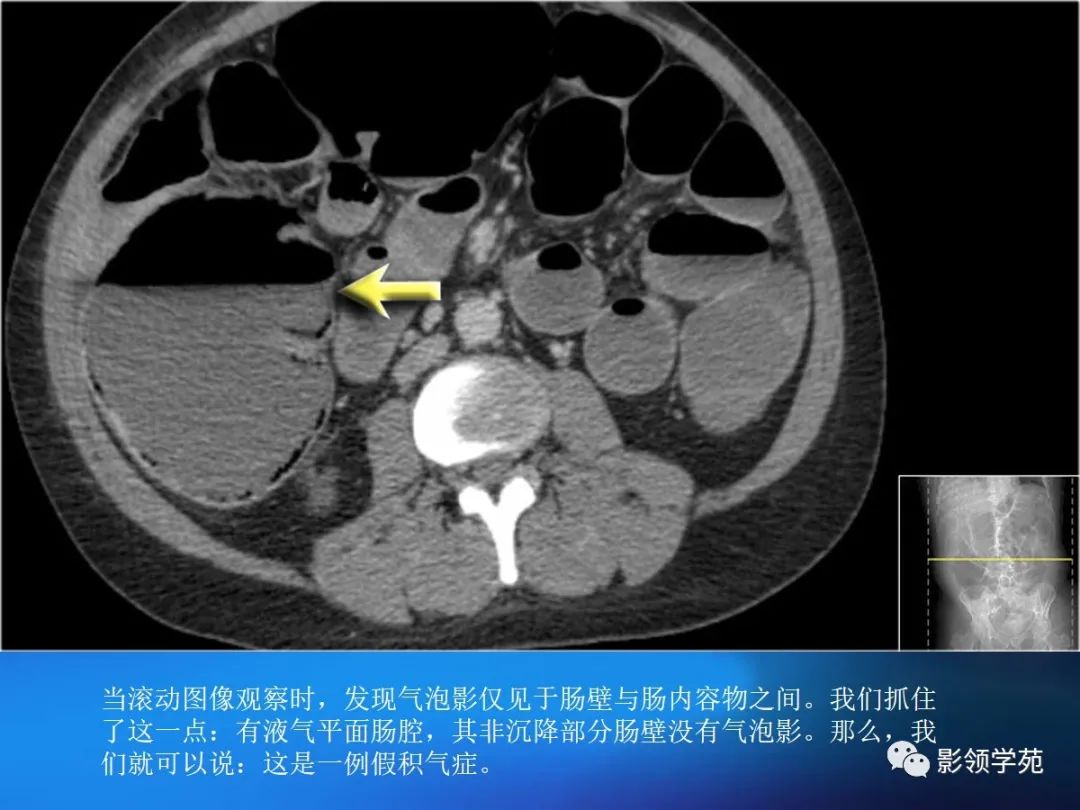

目前尚缺乏统一标准,一般认为,排除肠管充盈不佳或肠壁收缩时导致的假象后,当肠壁大于3mm是即考虑增厚。